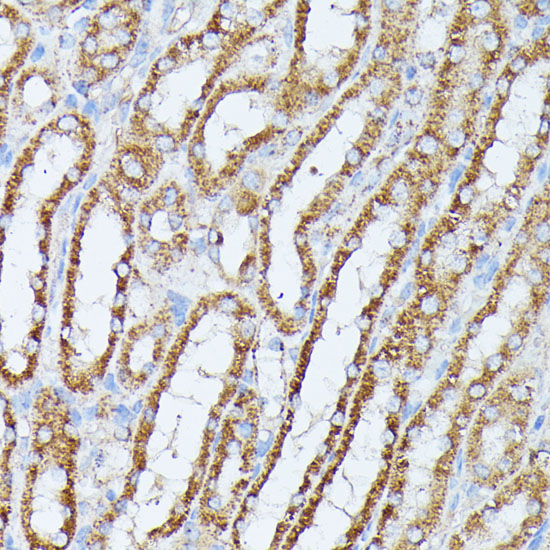

Immunohistochemistry of paraffin-embedded rat kidney using PPP2CB antibody at dilution of 1:100 (40x lens).

Immunohistochemistry of paraffin-embedded human colon carcinoma using PPP2CB antibody at dilution of 1:100 (40x lens).

Immunohistochemistry of paraffin-embedded mouse kidney using PPP2CB antibody at dilution of 1:100 (40x lens).